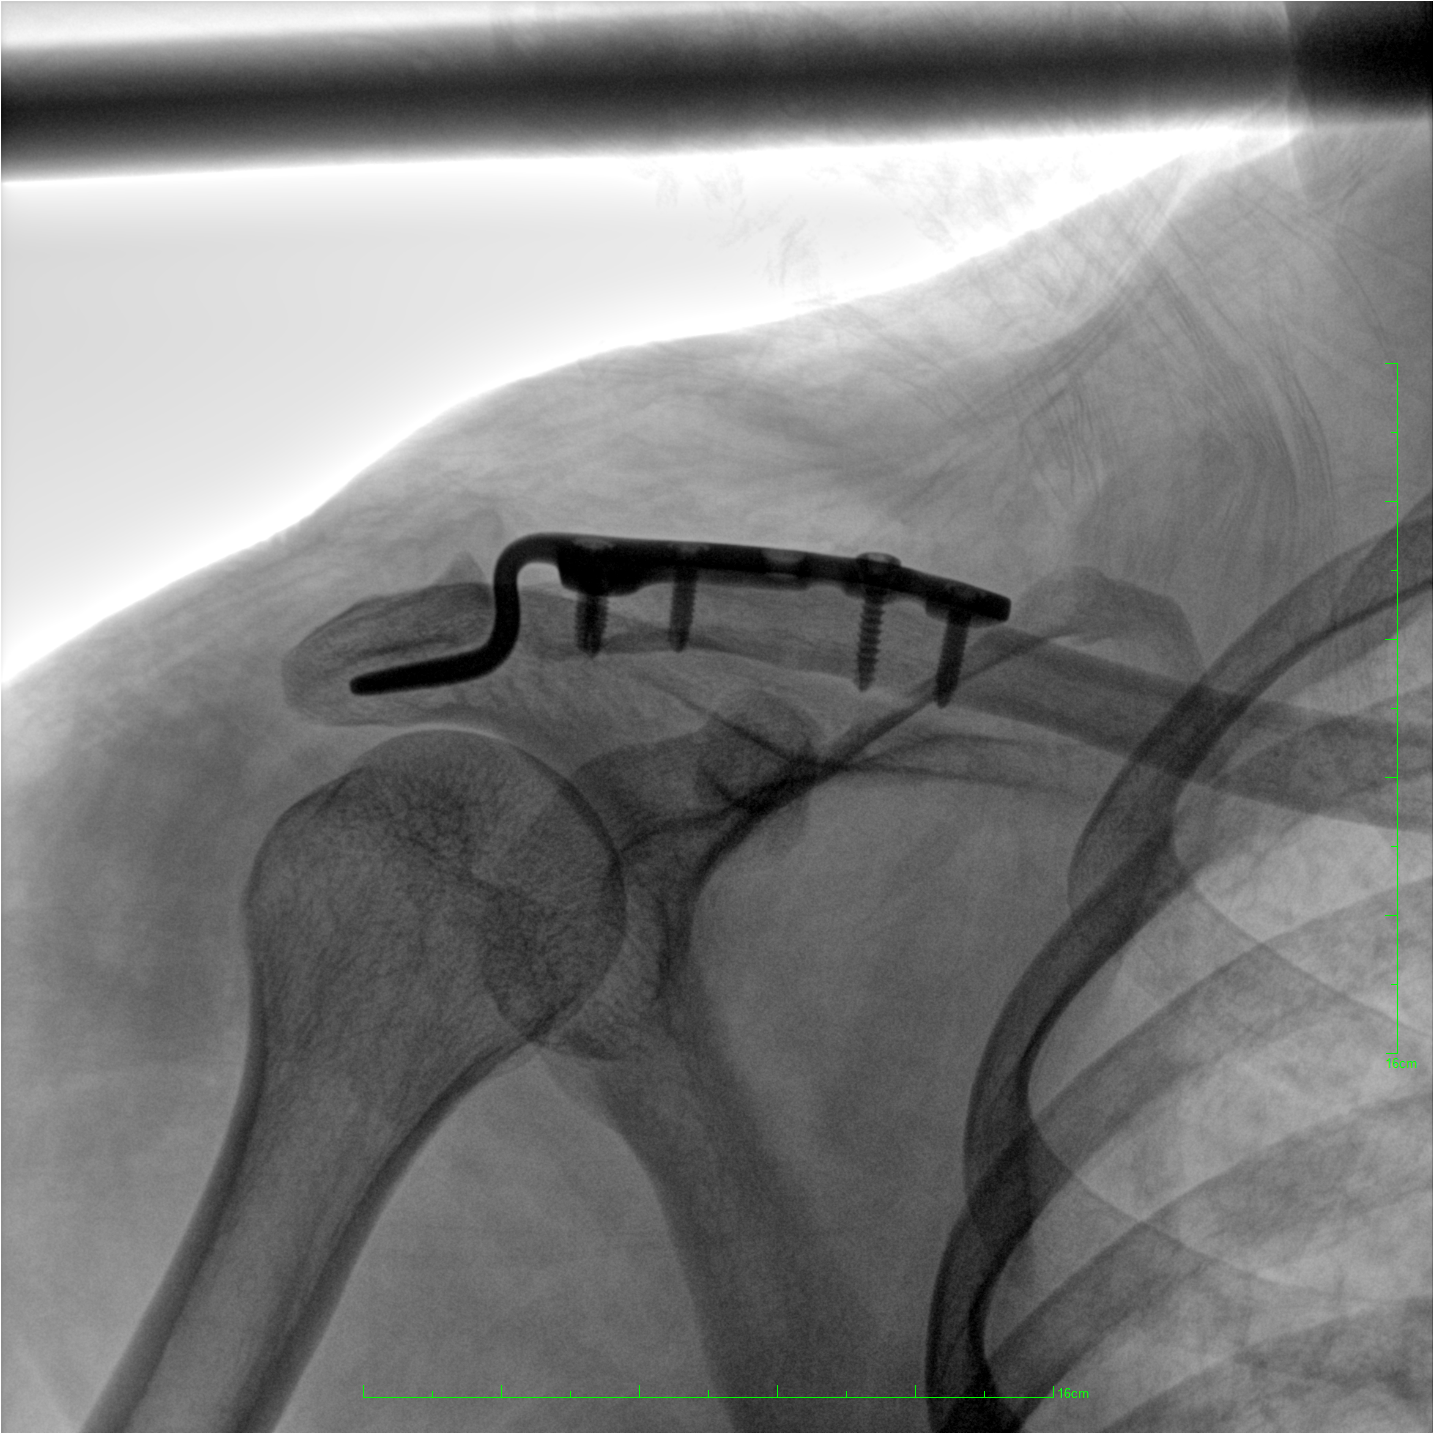

術(shù)中三維成像和橫斷面圖像提供多角度的手術(shù)診斷信息,輔助醫(yī)生進行術(shù)中評估判斷,諸如骨折復(fù)位情況和內(nèi)植入螺釘?shù)某叽绾臀恢?,輔助手術(shù)更好地完成。

提供更大的術(shù)中三維成像視野,采集更多圖像信息,可一次拍全全段頸椎、全段腰椎、七節(jié)胸椎、雙側(cè)骶髂關(guān)節(jié)、股骨頭及單側(cè)盆骨。